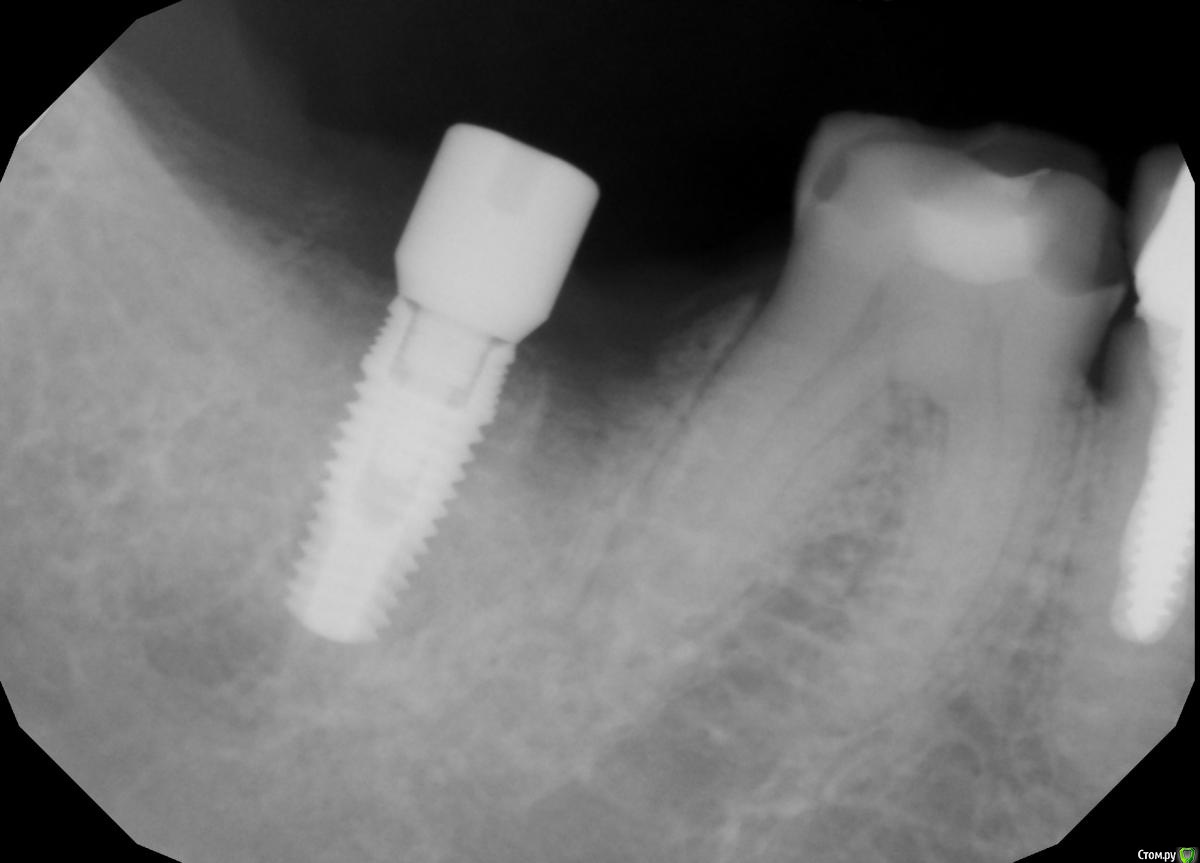

Demerchyan26 Опубликовано 3 марта, 2016 Автор Поделиться Опубликовано 3 марта, 2016 С десной будем работать, есть дефицит, в этот день видимо не с той ноги встал)))Только что снимок, у другой пациентки, тоже без графта, срок 2 месяца, сегодня ставили в другом сегменте, решил сделать снимок. Ссылка на комментарий